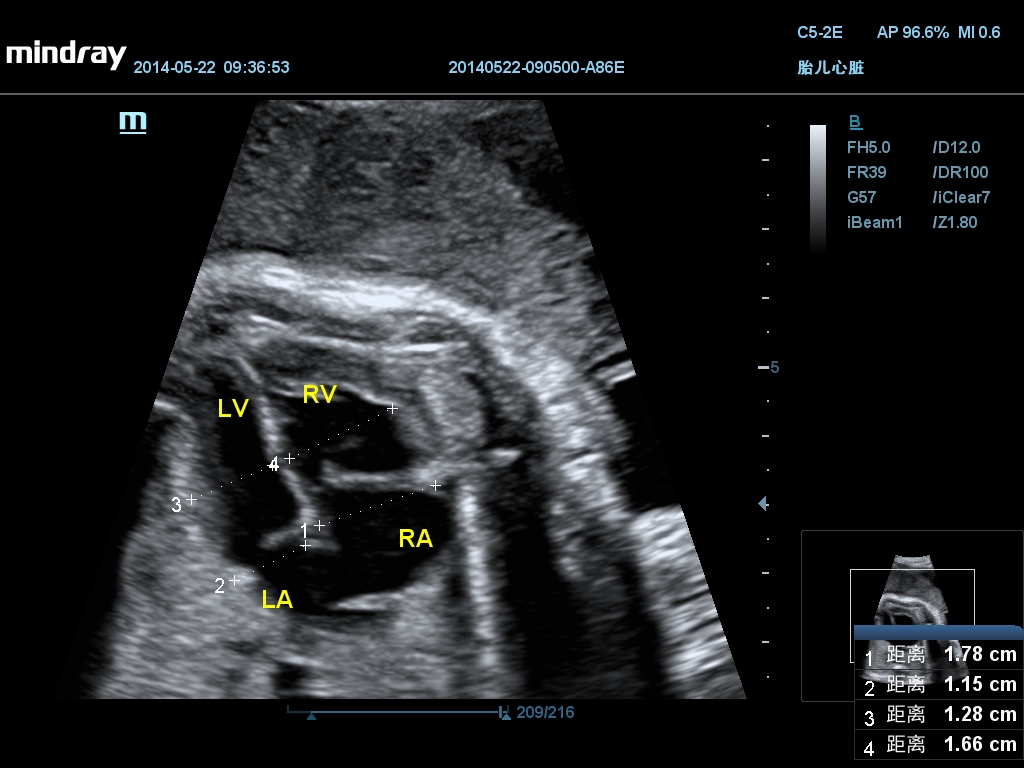

• Кардиология

• Гинекология и акушерство